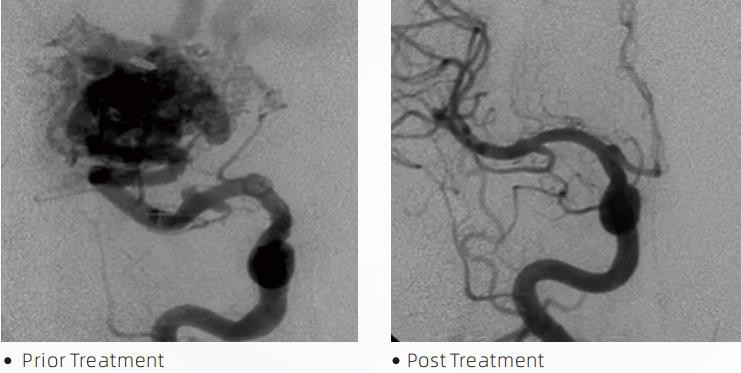

더 라바TM액체 색전 시스템은 뇌혈관 기형 치료를 위한 중재적 혈관내 치료법입니다. 뇌혈관기형은 두개내 출혈, 뇌경색, 뇌허혈 및 기타 질병을 유발할 수 있는 양성 또는 악성 신경혈관 이상을 말합니다. 액체 색전술 장치는 특수한 수액물질을 주입하여 비정상 뇌혈관을 색전시키는 간단한 혈관내 삽입을 통해 투여되는 의료기기이다. 유체 물질은 혈관 내에서 조절된 조직 색전증을 형성하여 뇌혈관 기형이 환자에게 미치는 영향을 줄일 수 있습니다. 신경혈관에 사용하도록 표시된 DMSO 호환 전달 마이크로 카테터를 사용하여 색전술 부위에 접근합니다. Lava 액체 색전제는 DMSO(디메틸 설폭사이드)에 용해된 EVOH(에틸렌 비닐 알코올) 공중합체와 현탁된 미세화된 탄탈륨 분말로 구성된 비접착성 액체 색전제 시스템으로 투시법 하에서 시각화를 위한 대비를 제공합니다. 용암TMLAVA-12, LAVA-18 및 LAVA-34의 세 가지 제품 구성으로 제공됩니다. LAVA-12: 원위 미세 혈관에 작은 공급 장치를 통해 공급할 때 권장됩니다. LAVA-18: 척추경 주사를 니더스 근처에서 실시할 때 권장됩니다. LAVA-34: 더 높은 흐름과 더 큰 주먹이 있는 구성 요소를 색전하는 데 권장됩니다.